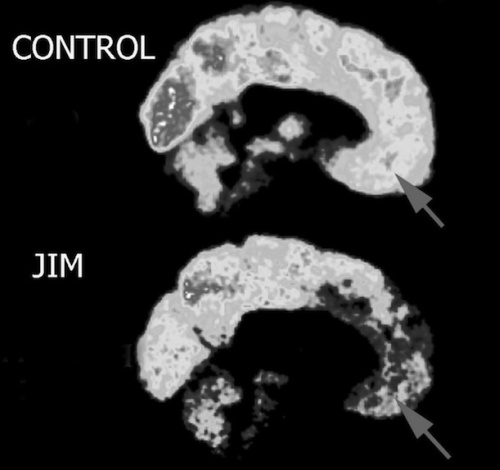

神経科学者のジェイムズ・ファロンは大学の研究の一環として、色々な人の脳波パターンを調べていたそうです。

そのうちのある脳スキャン画像を見た際に、サイコパスの構造的特徴を持つ画像を発見。

その画像の主を調べたところ、なんと自分の脳スキャン画像だったとのこと。

サイコパスは共感性やモラル、自制などに関係している前頭葉や側頭葉の活動が低い傾向があるそうです。

ジェイムズ・ファロンは「前頭葉や側頭葉の精神病質が殺人行動に影響する」という仮説を疑い、自分の遺伝子を検査。

しかしその結果は、攻撃性や暴力性、低い共感性という結果となったそうです。

そこで自分の家族を調べたところ、過去に父親と継母殺害で捕まった人物が母方の家系にいたとのこと。

しかしジェイムズ・ファロン自身は犯罪とは縁がなく、普通に結婚して幸せな家庭を築いていることから、

サイコパスには遺伝要因の他に環境要因もあると主張しています。

ここでジェイムズ・ファロンが言うサイコパスとは、犯罪的サイコパスのことでしょう。

彼は非犯罪的サイコパスになる可能性もあったと思いますが、

育ちのおかげでその素質は芽生えずに済んだようです。